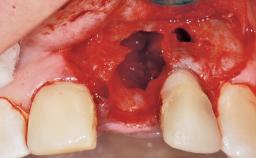

A 33-year-old female patient presented with an upper left central incisor that required extraction after a failed endodontic therapy. The tooth had been traumatized when the patient was a teenager and had undergone several endodontic treatments, including two apicectomy procedures. The patient was in good health and did not smoke. Clinical examination showed that the patient had a high lip line. In full smile, the gingival margins of the upper teeth were visible to the first molars. The gingival margins of central incisors 11 and 21 were only just showing. Examination of tooth 21 confirmed that the tooth was mobile and had hypererupted by 1 mm.

Bone Augmentation Horizontal|Simultaneous

Augmentation Materials Xenogenous|Membrane

Soft Tissue Grafting Simultaneous

Soft Tissue Anatomy Intact Defective

Soft Tissue Contour and Volume Slightly compromised